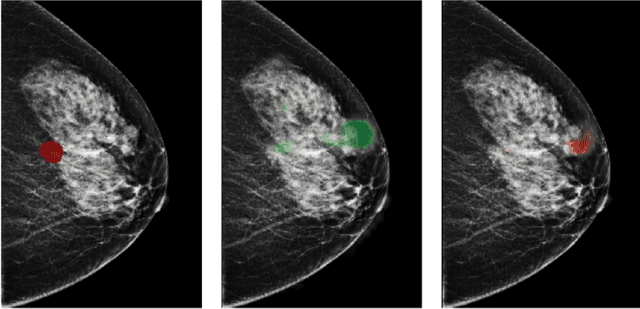

Abstract:Breast cancer is the most common cancer in women, and hundreds of thousands of unnecessary biopsies are done around the world at a tremendous cost. It is crucial to reduce the rate of biopsies that turn out to be benign tissue. In this study, we build deep neural networks (DNNs) to classify biopsied lesions as being either malignant or benign, with the goal of using these networks as second readers serving radiologists to further reduce the number of false positive findings. We enhance the performance of DNNs that are trained to learn from small image patches by integrating global context provided in the form of saliency maps learned from the entire image into their reasoning, similar to how radiologists consider global context when evaluating areas of interest. Our experiments are conducted on a dataset of 229,426 screening mammography exams from 141,473 patients. We achieve an AUC of 0.8 on a test set consisting of 464 benign and 136 malignant lesions.